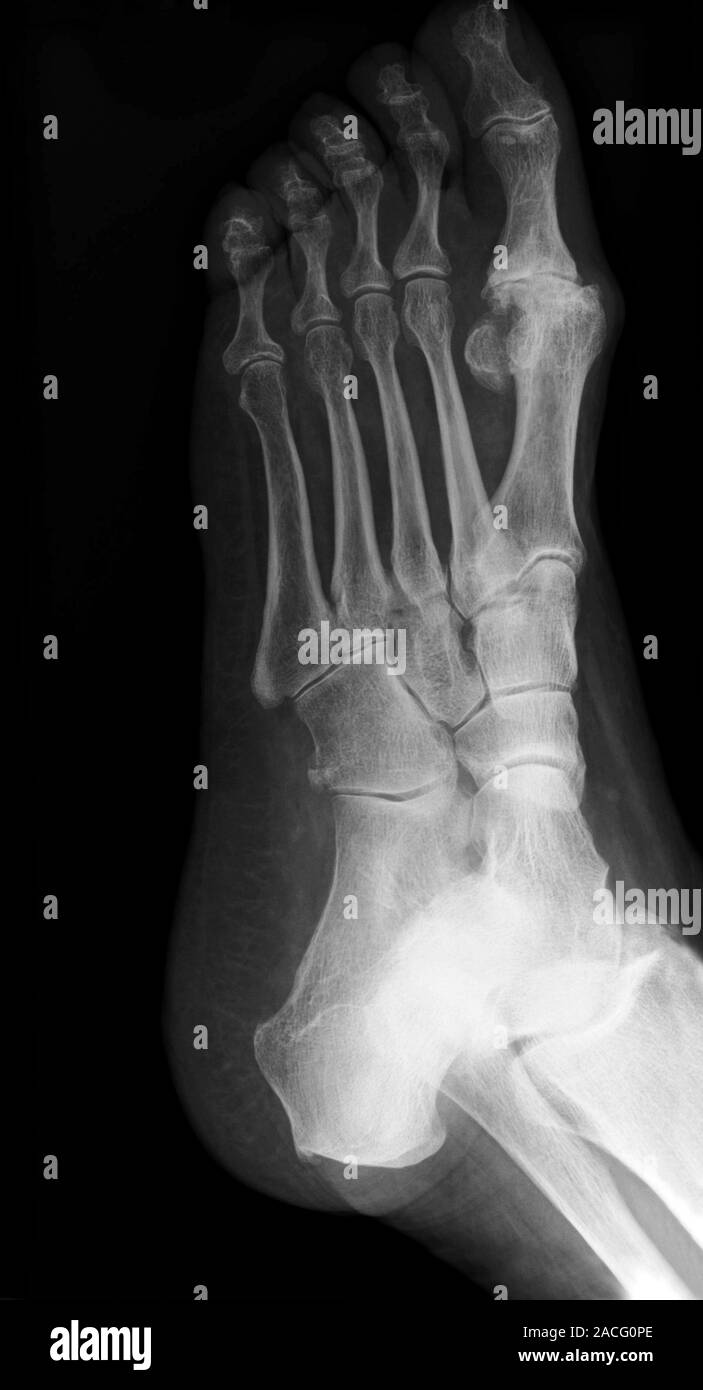

From www.alamy.com

Xray (oblique view) of the left foot of a patient, showing Osteoarthritis Big Toe Operation Whilst still in hospital, you’ll be shown how to walk using crutches and a surgical sandal. How long does it take to recover? Hallux rigidus means “stiff big toe” — the condition’s most common symptom. Osteoarthritis of the big toe joint is a progressive disease. The early stage of big toe arthritis is called hallux limitus, a condition where the. Osteoarthritis Big Toe Operation.